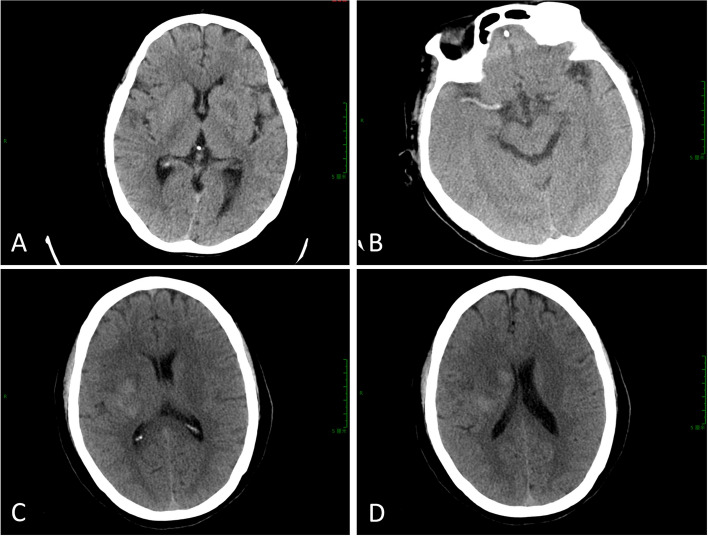

Results: Compared with the non-HT group, the proportion of atrial fibrillation history in the HT group was significantly increased, and the National Institute of Health Stroke Scale (NIHSS) score and galectin-3 (Gal-3) level were significantly increased before thrombectomy (P < 0.01). Compared with the non-HT group, the proportion of exudation of contrast medium and Hyperdense Middle Cerebral Artery Sign (HMCAS) in the HT group was significantly increased, time to peak (TTP) was significantly prolonged, and cerebral blood flow (CBF) was significantly decreased (P < 0.001). The history of atrial fibrillation, NIHSS score before thrombectomy, Gal-3, contrast agent exudation, HMCAS, TTP and CBF were the influencing factors of postoperative HT after mechanical thrombectomy in AIS-LVO (P < 0.05). Based on the results of multivariate logistic regression analysis, a prediction model was established as follows: Logit (P) = -3.520 + 1.529 × history of atrial fibrillation + 0.968 × NIHSS score before thrombectomy + 0.806 × Gal-3 + 1.134 × contrast agent exudation + 2.146 × HMCAS + 0.684 × TTP-0.725 × CBF. The area under the curve (AUC) of the logistic prediction model for predicting HT after AIS-LVOLVO mechanical thrombectomy was 0.873 (95% CI 0.817-0.929) with a sensitivity of 78.75% and a specificity of 83.33%, indicating that the prediction model had good prediction efficiency. The AUC of TTP and CBF alone in predicting HT after mechanical thrombectomy in AIS-LVO patients was 0.728 and 0.736, respectively. The AUC of combined detection was 0.783, and the combined detection had a high diagnostic value for HT after mechanical thrombectomy in AIS-LVO patients.

Conclusion: The combined detection of TTP and CBF of CT imaging features had certain diagnostic value for HT in AIS-LVO patients after mechanical thrombectomy. The logistic prediction model based on these influencing factors had a high diagnostic value for HT after mechanical thrombectomy.